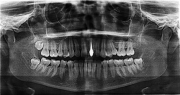

2.診査・診断・術前治療

全身の健康状態や人工歯根を植え込むだけの顎の骨があるか、お口の中の状態はどうか等を十分に調べます。 虫歯や歯周病など問題があれば術前に治療を行います。